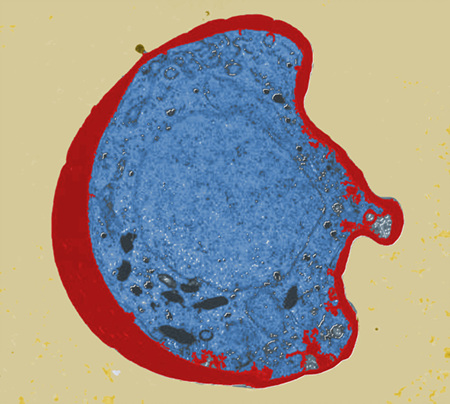

¸ð±â°¡ ¿Å±â´Â ¹«¼­¿î º´ ¡®¸»¶ó¸®¾Æ¡¯

<»çÁø¼³¸í = ¸»¶ó¸®¾Æ ¿øÃæ(ÆÄ¶õ»ö)ÀÌ ÀûÇ÷±¸(ºÓÀº»ö) ¾ÈÀ¸·Î µé¾î°¡ ÀÚ¸® Àâ°í ÀÖ´Â ¸ð½ÀÀ» ÀüÀÚÇö¹Ì°æÀ¸·Î ÃÔ¿µÇß´Ù. 5000¹è È®´ë> ¿©¸§Àº ³ëÃâÀÇ °èÀýÀÌ´Ù. ´õ.... ¤ÓÀ̹̳ª ±âÀÚ 2009-08-06